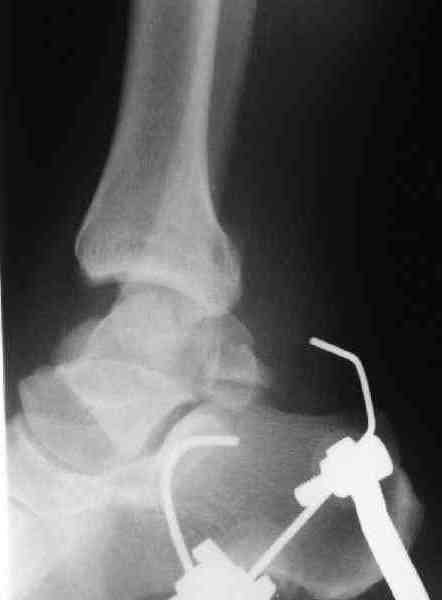

повторили рентгенограммы и доделали проекции, к единому мнению все еще не пришли

На ренгенограмме не уловил многоскольчатость тарана, чтобы доказать, конечно, можно было исследовать на КТ, потом КТ дает ориентацию фрагментов.

Два фрагмента суставной поверхности тарана можно восстановить боковой компрессией шурупами и дополнительно костная пластика.